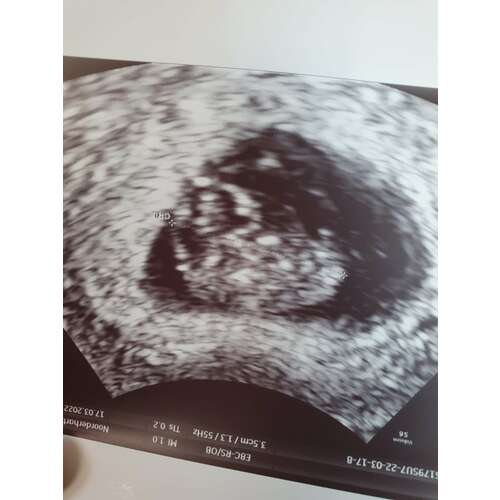

7+6

Gefeliciteerd met je zwangerschap! Dit was mijn 8 weken echo.